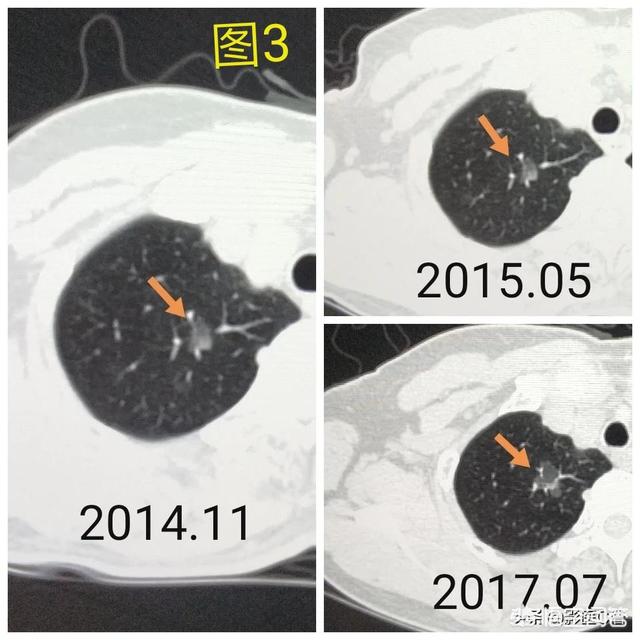

Bei diesem Beispiel, das 4 Jahre lang beobachtet wurde, wuchs der Klumpen immer weiter.

Der nächste Schritt bei der Entdeckung von Lungenknoten ist die Feststellung, ob sie gutartig oder bösartig sind. Gutartige Knoten sind definitiv nichts, wie z. B. Lymphknoten in der Lunge, missgebildete Tumore, sklerosierende Pneumozytome usw. Bösartige Knoten sollten aggressiv behandelt werden. Die verbleibenden Knoten können gut- oder bösartig sein, und das allgemeine Prinzip der Behandlung solcher Knoten besteht darin, eine Nachuntersuchung zu empfehlen, wobei der Zeitraum für die Nachuntersuchung je nach den Besonderheiten des Knotens (Morphologie, Größe, Dichte usw.) zwischen 3 Monaten und 1 Jahr liegt. Einige Knoten können sich während der Nachuntersuchung auflösen und verschwinden, wie z. B. entzündliche Knoten, während andere unverändert bleiben können, wie z. B. Granulome, was eine gute Information ist. Wenn bei der Nachuntersuchung bösartige Anzeichen auftreten, wie z. B. eine Vergrößerung des Knotens, eine Zunahme von echten oder festen Bestandteilen im Glasschliffknoten, eine Verdichtung des Knotens oder das Einwachsen von peripheren Blutgefäßen usw., dann sollten wir aggressiv dagegen vorgehen. In der Tat, genau wie der Blick auf die Menschen, ein Gesicht der Rechtschaffenheit ist in der Regel gute Menschen, wilde und bösartige schlechte Menschen, und einige vorübergehende kann nicht gesehen werden, nur durch die Beobachtung der Person, das Verhalten, wenn die Regeln sind in der Regel keine Angst vor, und wenn Sie feststellen, dass es ein schlechtes Verhalten sollte mit in einer fristgerechten Weise behandelt werden. Abbildung 1, fand die linke obere Lunge Glasschliffknötchen (orange Pfeil), Follow-up für mehr als zwei Jahren ohne Veränderung. Abbildung 2: Zwei kleine Glasschliffknötchen in der rechten oberen Lunge (orangefarbene Pfeile), die nach zwei Jahren verschwunden sind. Abbildung 3: Glasschliffknoten in der rechten oberen Lunge, der sich bei der dritten Nachuntersuchung vergrößert hat, und es wird empfohlen, ihn durch eine chirurgische Pathologie des Carcinoma in situ, d. h. der Krebsvorstufe, zu behandeln, um den Lungenkrebs wirklich im Keim zu ersticken.